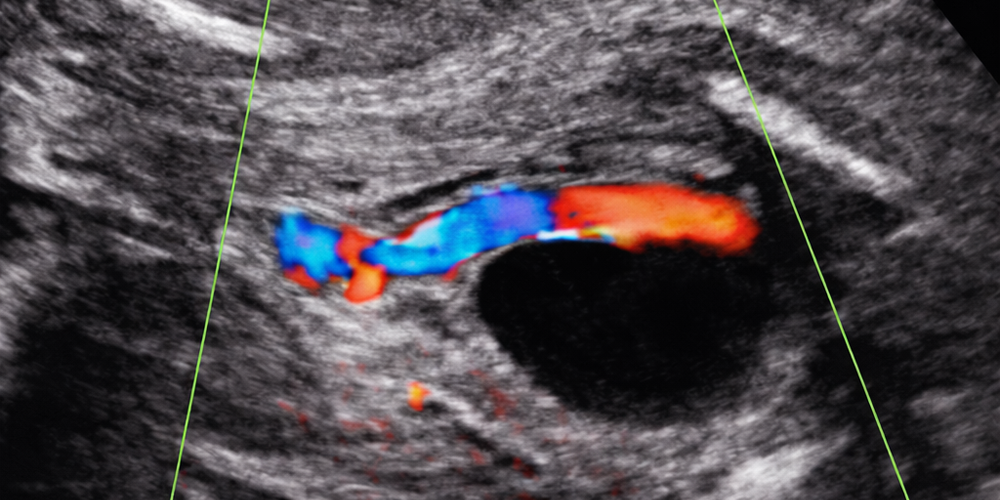

Göbek atardamarları bebeğin karnına girer girmez idrar torbasının iki yanından geçerek dolaşıma kan taşırlar. Doğumdan sonra ise bu damarlar kuru ve sadece boş kalıntıları kalır. Anne karnındaki muayene sırasında yukarıdaki resimdeki gibi renkli akım kontrol edilecek olursa idrar torbasının bir yanında olan damarın diğer eşinin olmadığı, yani tek umblikal arter olduğu kolayca izlenmektedir. Bebek doğup göbek kordonu kesildikten sonra zaten göbeği kuruyup düşecek üç damarlı olsa ne olur iki damarlı olsa ne olur?